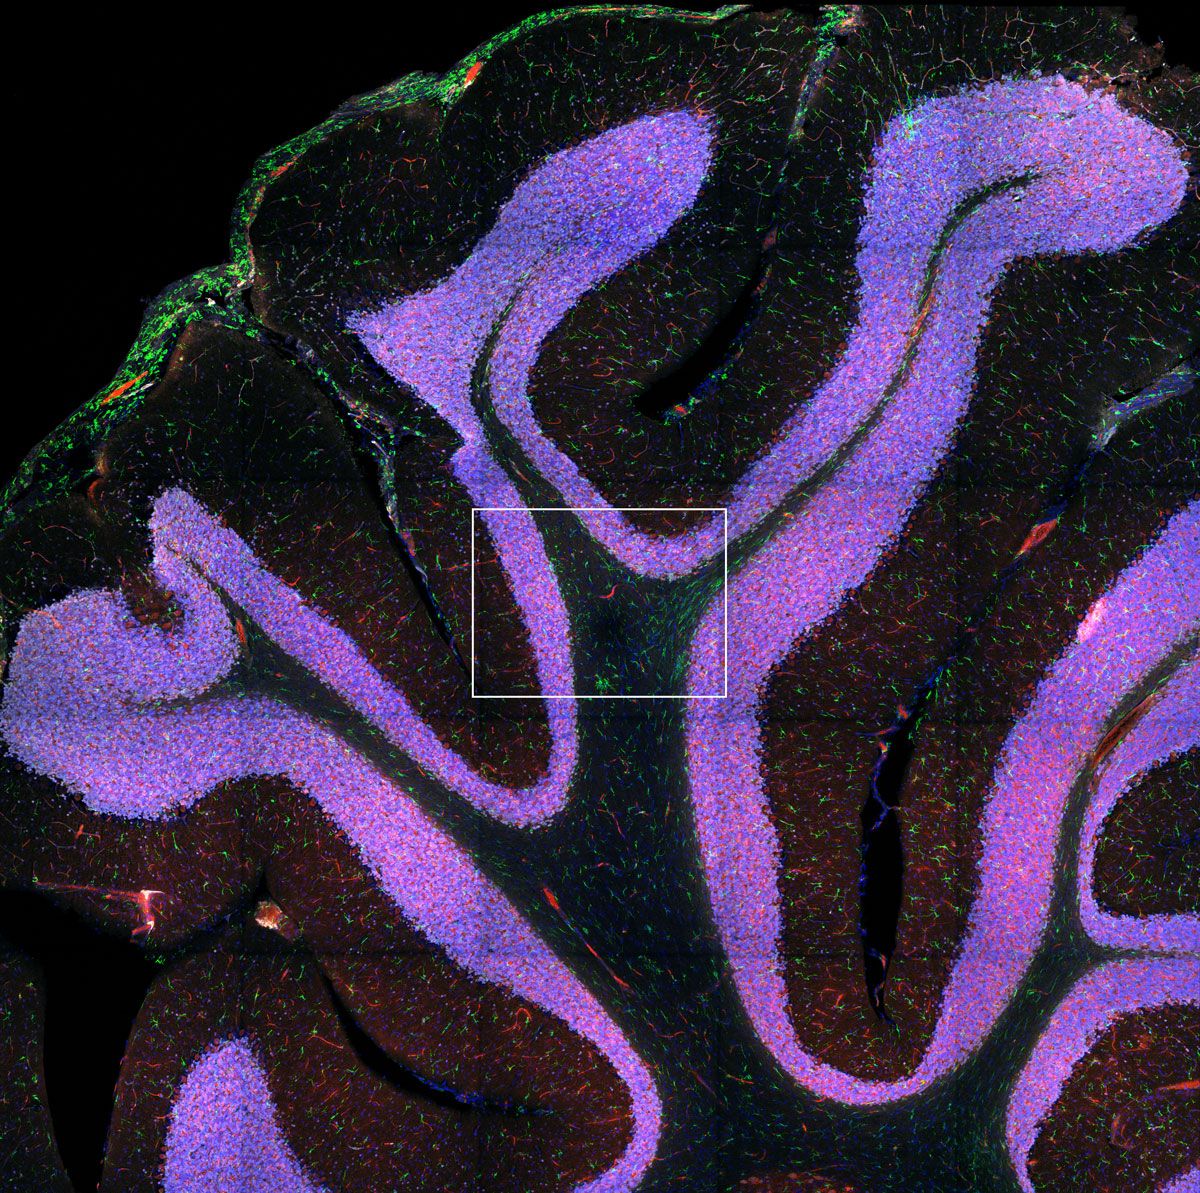

Neurofilament-heavy chain (NFH) in green, myelin basic protein (MBP) in red, glutathione S-transferase pi 1 (GSTpi) in blue. Mouse cerebellum captured with a UPLXAPO40X objective.